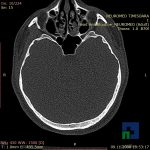

În cazul traumatismelor cranio-cerebrale:

- Evaluarea deplasării liniei mediane

- Evaluarea cisternelor perimezencefalice

- Diagnosticul edemului cerebral, a contuziei cerebrale, a leziunilor axonale difuze edematoase/hemoragice, a dilacerării cerebrale, a hematomului intraparenchimatos posttraumatic, a hematoamelor subdurale/extradurale (acute, subacute, cronice), a hemoragiei intraventriculare, a hemoragiei subarahnoidiene

- Diagnosticul traumatismelor de bază de craniu

- Diagnosticul fistulei LCR

- Diagnosticul herniilor cerebrale